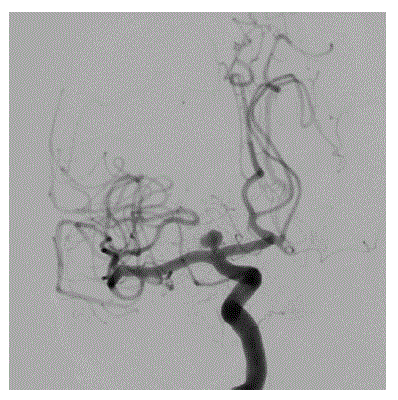

Assinale a alternativa que corresponde à CORRETA topografia do aneurisma cerebral na angiografia abaixo.

enunciado 1740766-1